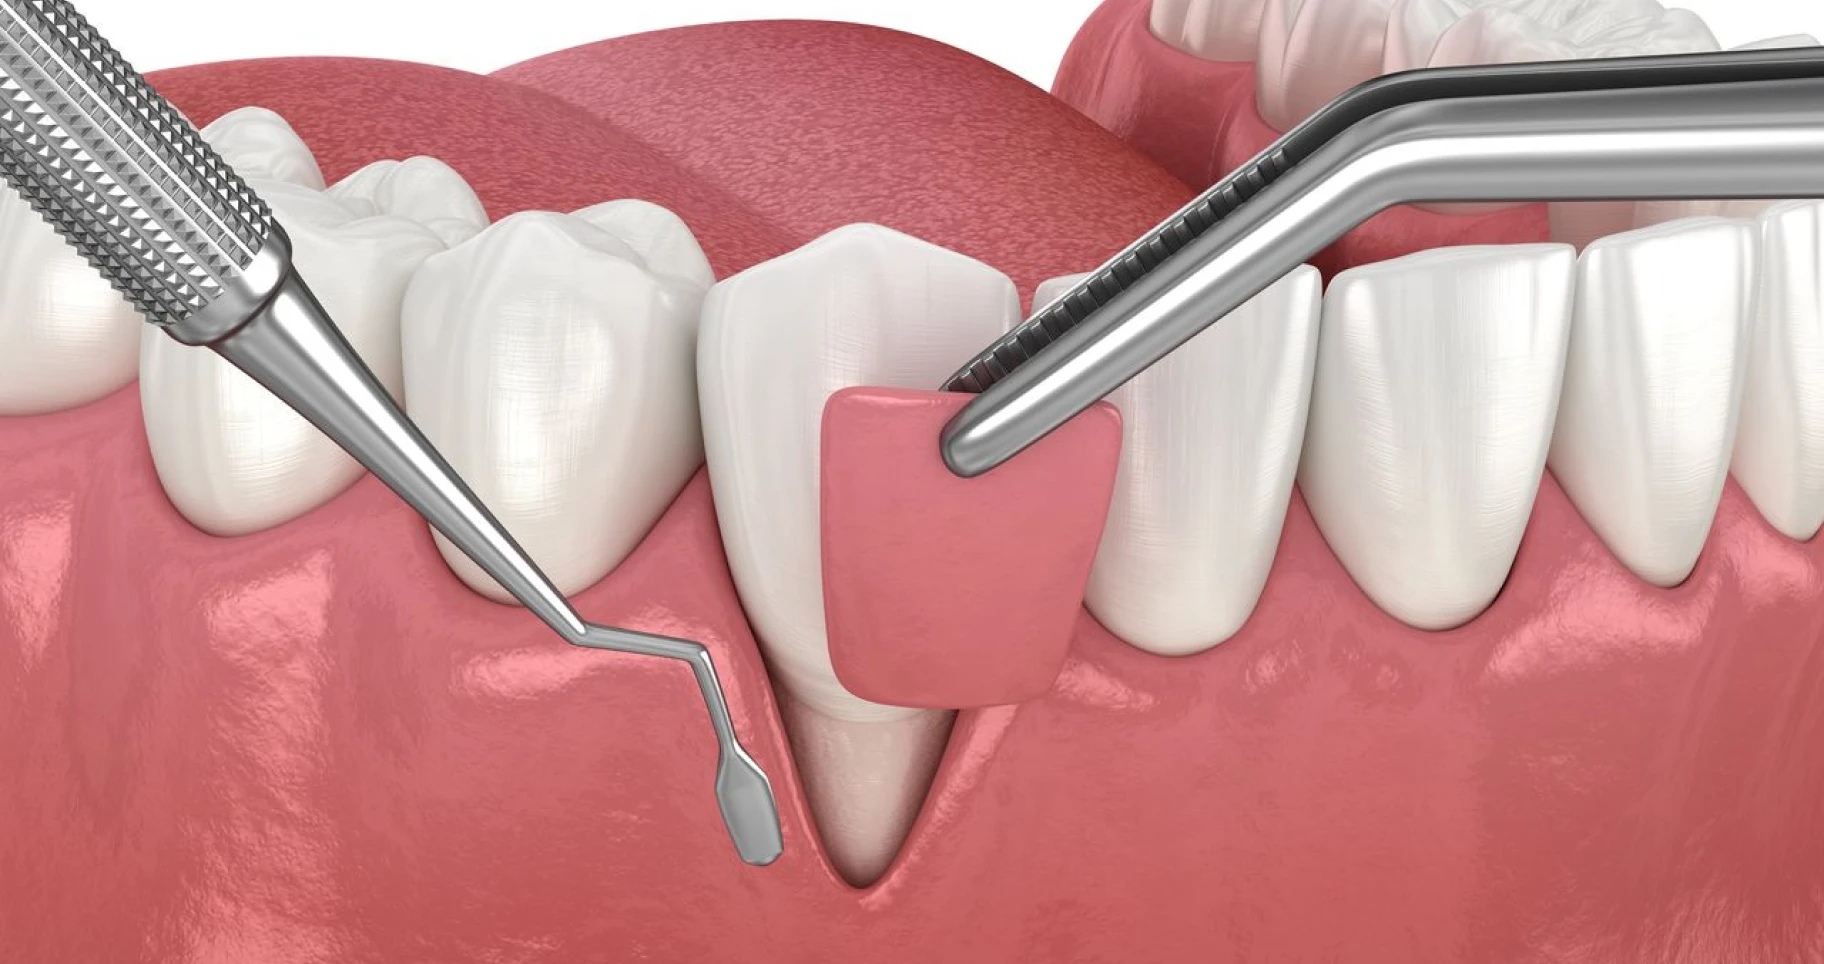

Surfaçage radiculaire : guide du traitement et conseils